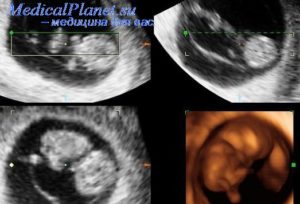

1. УЗИ, которое выполняется в 20 недель, а при подозрении на патологию плаценты – в 26, 32 и 36 недель гестации.

2. Исследование плацентарного кровотока с помощью допплерографии, может выполняться при обычном или трансвагинальном УЗИ.

УЗИ, в частности, помогает определить трисомию плода по 18 хромосоме (синдром Эдвардса), сопровождающуюся не только нарушениями развития и самопроизвольным выкидышем, но и плацентарными изменениями.

Размеры плаценты оказывают влияние на развитие плода, являясь одним из критериев диагностики здоровья ребёнка и матери. Определяют толщину после 4 месяца беременности на ультразвуковом исследовании. Размер плаценты в нормальном состоянии соответствует количеству недель плюс 1,5–2 мм в среднем. Увеличение толщины происходит до 36 неделе и составляет к этому времени 35,6 мм.

На начальной стадии развития утолщение или гиперплазия проходит бессимптомно. Определить симптомы начального этапа патологического процесса можно только с помощью ультразвукового обследования.

Первые признаки отека плаценты во время беременности могут появиться уже на 15-й неделе. Однако самостоятельно симптомы дисфункции увидеть нельзя. Проблему можно выявить только на ультразвуковом исследовании. Отечность при этом заключается в утолщении стенок органа на 25-100%. Внешние же признаки патологии могут и вовсе отсутствовать.

После 18-й недели беременности проводят допплерометрию для исследования направления и скорости кровообращения плода и детского места.

На поздних сроках в результате отека может наблюдаться неправильное сердцебиение плода (учащение или снижение сердечных сокращений), а также изменение в шевелении ребенка. В этот период для точного обследования используется кардиотокография (КТГ).

Если на УЗИ выявлена гиперплазия плаценты, то женщине придётся сдать ряд анализов таких, как анализ мочи на белок, крови на уровень сахара, общий, биохимический, тесты torch и rpr.